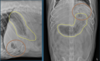

What is shown in these images?

A

Left: normal; normal margin

Middle: diffuse infiltrate; rounded margin

Right: focal mass; enlarged, lumpy margin